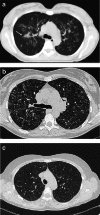

Objectives: Pulmonary Langerhans cell histiocytosis (PLCH) is a rare interstitial granulomatous disease that usually affects young adults who are smokers. Chest computed tomography (CT) allows a confident diagnosis of PLCH only in typical presentation, when nodules, cavitated nodules and cysts coexist and predominate in the upper and middle lungs.

Methods: This article includes a pictorial essay of typical and atypical presentations of PLCH at initial chest CT. Various appearances of PLCH are illustrated and possible differential diagnosis is discussed.

Results: PLCH can present with some aspecific features that may cause diagnosis of the initial disease to be overlooked or other pulmonary diseases to be suspected. In cases of nodule presentation alone, the main differential diagnosis should include lung metastasis, tuberculosis and other infections, sarcoidosis, silicosis and Wegener's disease. In cases of cysts alone, the most common diseases to be differentiated are centrilobular emphysema and lymphangiomyomatosis. Clinical symptoms are usually non-specific, although a history of cigarette smoking, coupled with the presence of typical or suggestive findings at imaging, is key to suspecting the disease. Atypical presentations require surgical biopsy for diagnosis.

Teaching points: • PLCH is a rare interstitial smoking-related disease that usually affects young adults. • The typical first CT shows a mix of nodules, cavitary nodules and cysts in the upper-middle lungs. • Atypical appearance, either cysts or nodules alone, mandates that other diagnoses be considered. • Lung cystic involvement correlates with lung function abnormalities and predicts functional decline. • Integration of the clinical history and imaging results is key to diagnosis.